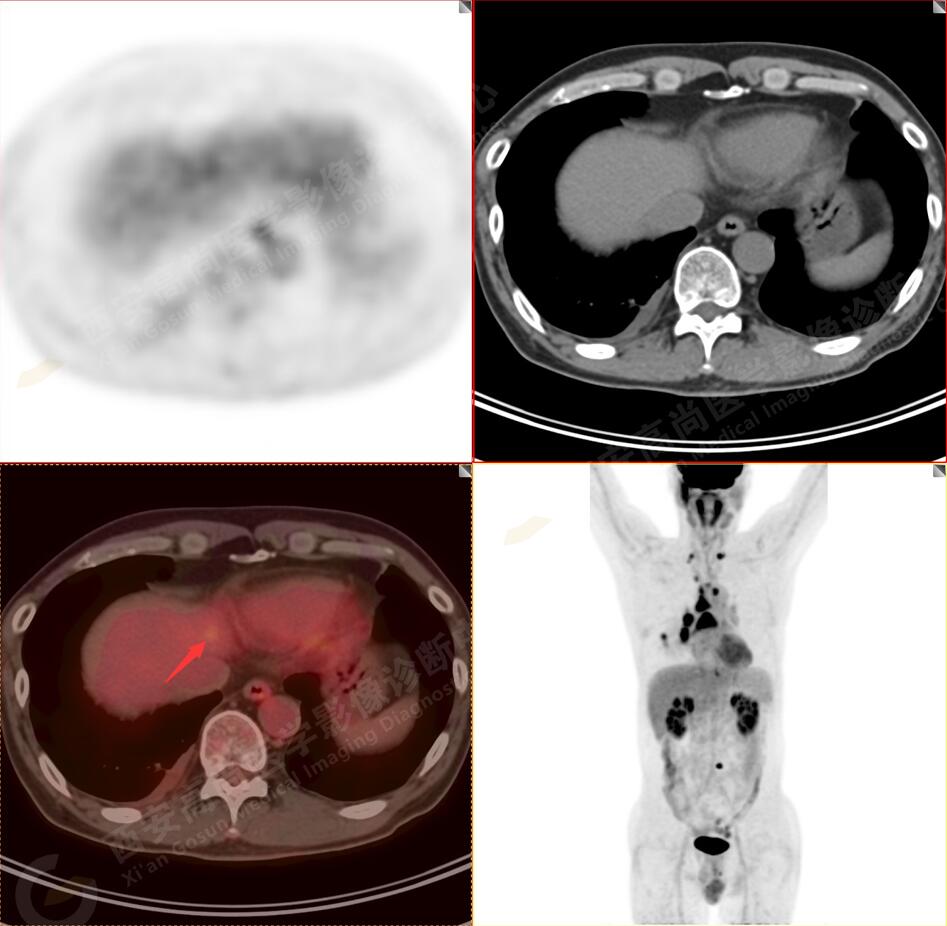

2.以下為全身多發(fā)轉(zhuǎn)移灶

4.右后胸膜輕度增厚,形成多個(gè)條狀軟組織病變,呈FDG代謝輕度異常增高,考慮為轉(zhuǎn)移性病變;右側(cè)胸腔微量積液。

5.腰4椎體左側(cè)緣溶骨性骨質(zhì)破壞,F(xiàn)DG代謝異常增高,考慮骨轉(zhuǎn)移瘤。